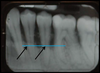

Comment mettre en évidence l’atteinte du niveau osseux

Seul l’examen radiographique permet de quantifier la perte osseuse et donc l’importance du déchaussement.

Atteinte superficielle

Atteinte sévère

Atteinte terminale